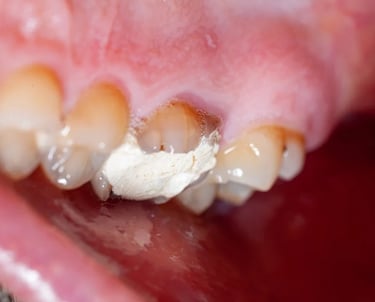

Se revisa si hay fracturas en la parte visible del diente. Las fracturas de la corona pueden ser causadas por trauma o caries extensas y pueden afectar el tratamiento endodóntico.

Evaluación de fracturas de la corona